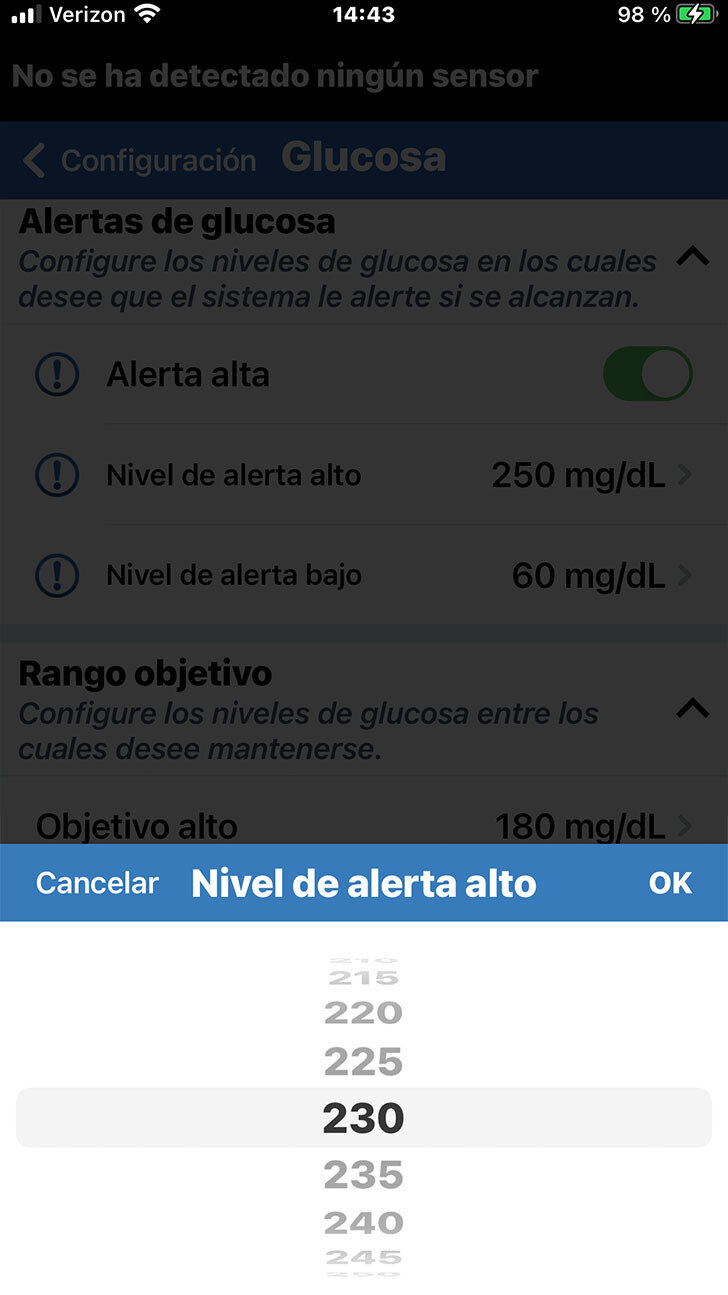

Tenga en cuenta que la configuración predeterminada es 250 mg/dL en el caso de la alerta de glucosa alta y de 65 mg/dL en el de la glucosa baja.

Cuando desee personalizar la configuración de una alerta de glucosa, solo deberá tocar el ajuste que desee modificar.

Desplácese al valor deseado. A continuación, toque OK.

Siempre analice con su profesional

de la salud la configuración de las alertas adecuada para usted.

Cuando desee personalizar la configuración de una alerta de glucosa, solo deberá tocar el ajuste que desee modificar.